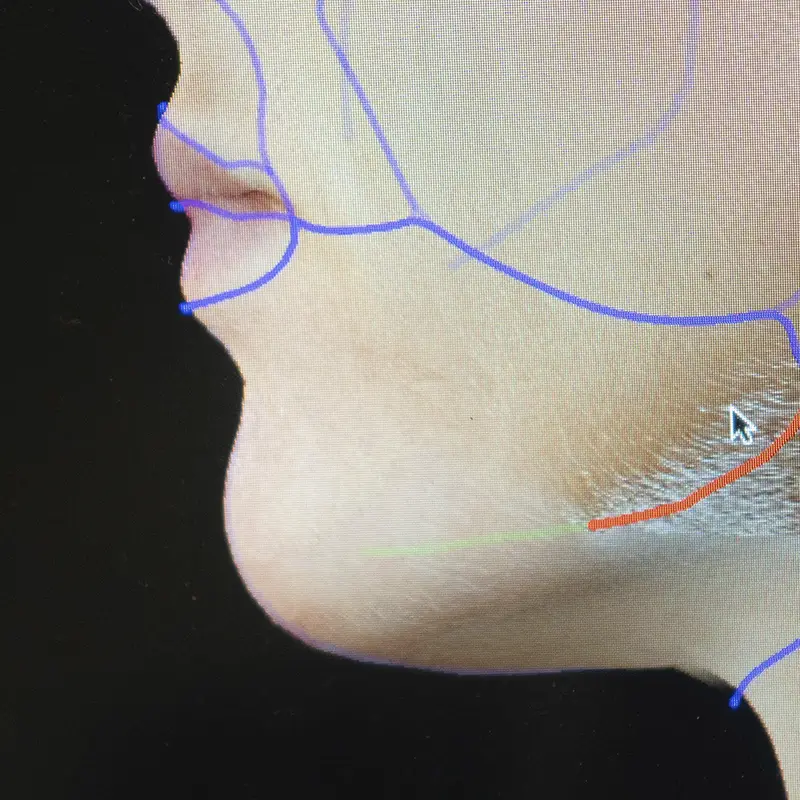

Últimas tecnologías

Disponemos de las tecnologías más avanzadas y los productos de mayor calidad, garantizando la seguridad y la eficacia de nuestros tratamientos, así como el cumplimiento de todas las normativas sanitarias vigentes.